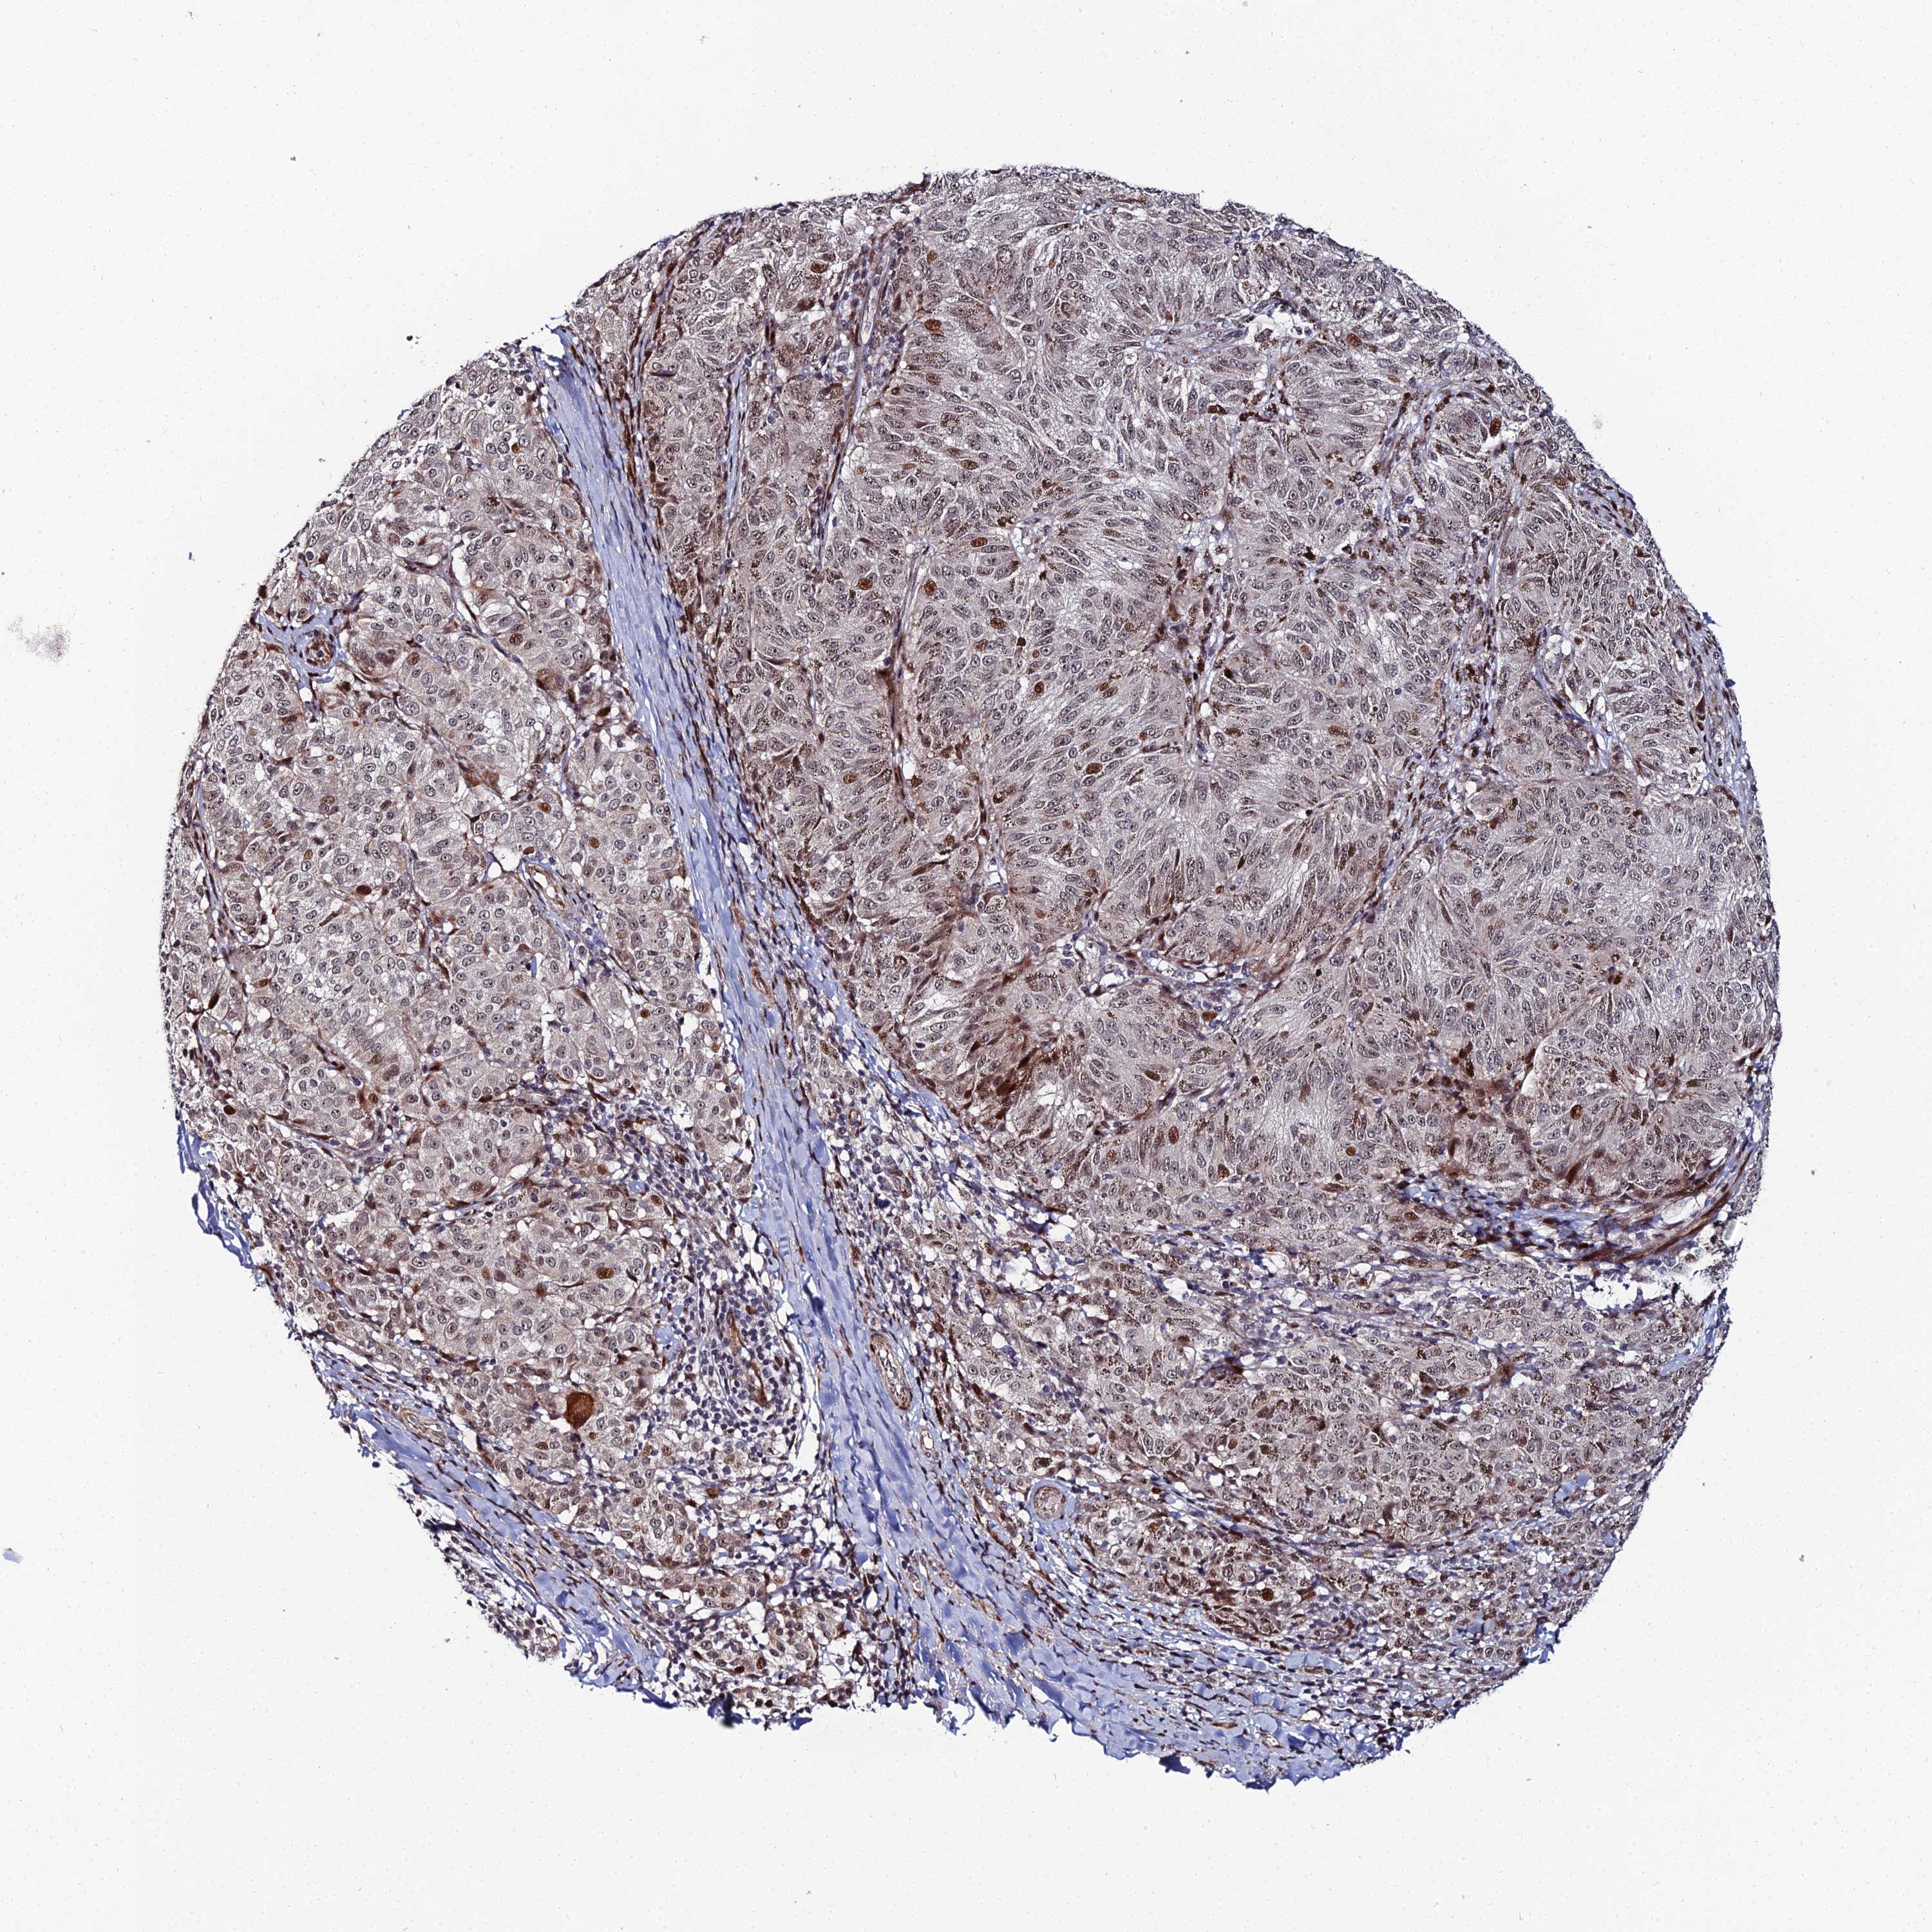

MELANOMA - Protein expressioni

A mouse-over function shows sample information and annotation data. Click on an image to view it in a full screen mode. Samples can be filtered based on level of antibody staining by selecting one or several of the following categories: high, medium, low and not detected. The assay and annotation is described here.

Note that samples used for immunohistochemistry by the Human Protein Atlas do not correspond to samples in the TCGA dataset.

Antibody stainingi

Antibody staining in the annotated cell types in the current human tissue is reported as not detected, low, medium, or high, based on conventional immunohistochemistry profiling in selected tissues. This score is based on the combination of the staining intensity and fraction of stained cells.

Each image is clickable and will lead to virtual microscopy that enables deeper exploration of all samples and also displays staining intensity scores, fraction scores and subcellular localization as well as patient and tissue information for each sample.

Antibody HPA043048

Staining

High

Medium

Low

Not detected

Intensity

Strong

Moderate

Weak

Negative

Quantity

>75%

75%-25%

<25%

None

Location

Nuclear

Cytoplasmic/membranous

Cytoplasmic/membranous,nuclear

Malignant melanoma, NOS

Malignant melanoma, Metastatic site